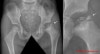

소아 대퇴골두 무혈성 괴사의 방사선 소견

- Waldenstrom의 시기적 단계

(1) Incipient or Synovitis Stage : 1-3wk

(2) Avascular or Aseptic Necrotic Stage : 6m-1y

(3) Regenerative or Fragmentation Stage : 1-3y

(4) Residual Stage or Reparative Stage